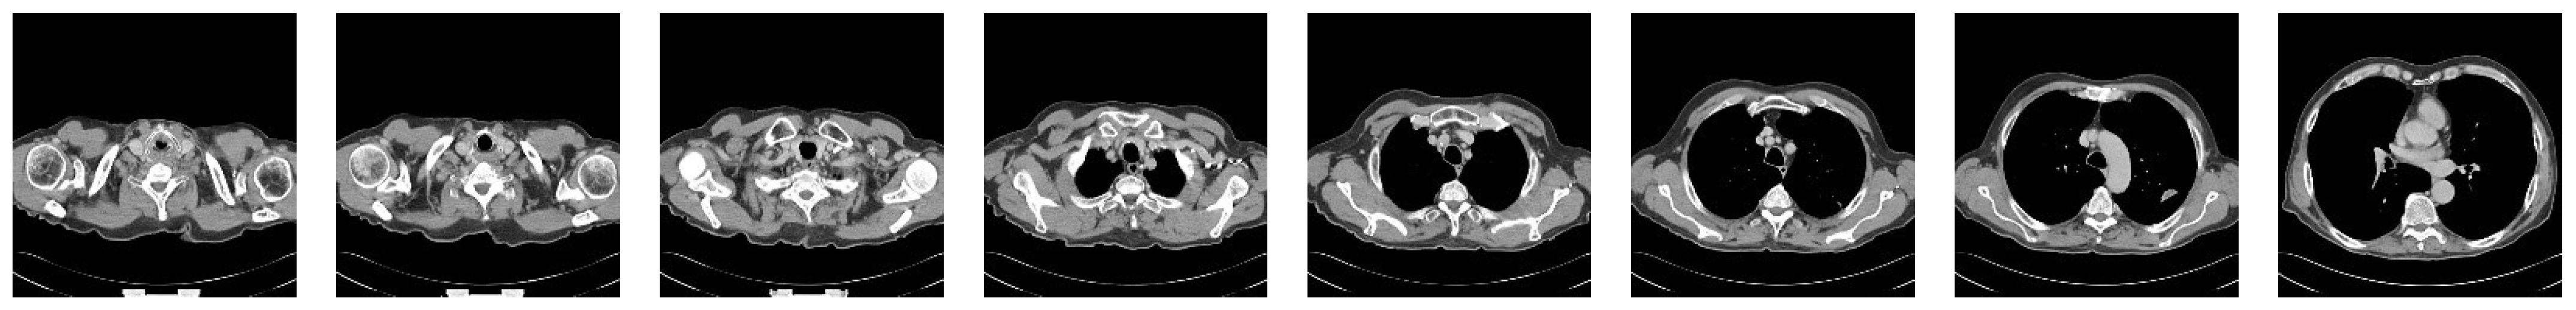

4.2. Medical Image Denoising